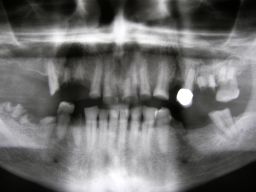

Hier ein einfacher Fall, bei dem keine besondere Vorbehandlung notwendig war. Der Patient, 58jährig, suchte die Praxis erstmals im September 2005 auf. Es erfolgten mehrere prothetische Planungen, der Gutachter des "Medizinischen Dienstes der Krankenkassen" (MDK) wurde noch von der Krankenkasse in Anspruch genommen, was heute bei größeren Planungen der Regelfall geworden ist. Umgesetzt wurde dann eine für einen solch großen Fall preisgünstige Lösung von 6434 Euro Gesamtkosten (4264 Laborkosten, 2170 Honorar). Die Krankenkasse übernahm als Festzuschuß 3843 , für den Patienten verblieben 2591. Im Januar 2006 ging es dann endlich los - zunächst allerdings beim Kieferchirurgen, weil wegen einer erhöhten, medikamentös bedingten Blutungsneigung es sicherer erschien, einige Zahnentfernungen von diesem durchführen zu lassen. Ausgangsbilder: |